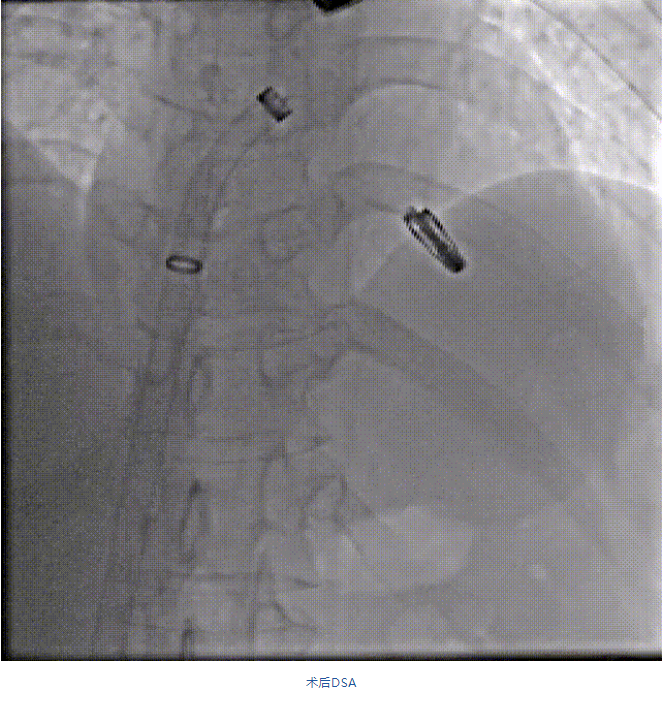

在阜外醫院潘湘斌教授團隊的支持下,手術經股靜脈-房間隔入路,采用全身麻醉插管,在TEE和DSA引導下完成房間隔穿刺。置入JensClip瓣膜夾系統后,在左房調整瓣膜夾的位置和軸向,后進入左室,在TEE引導下捕捉二尖瓣前后瓣葉,并關閉瓣膜夾。經TEE反復確認手術效果后最終鎖定并釋放瓣膜夾。術后即刻超聲顯示瓣膜夾位置穩定,功能良好,二尖瓣反流由術前4+減少至微量,手術圓滿成功。